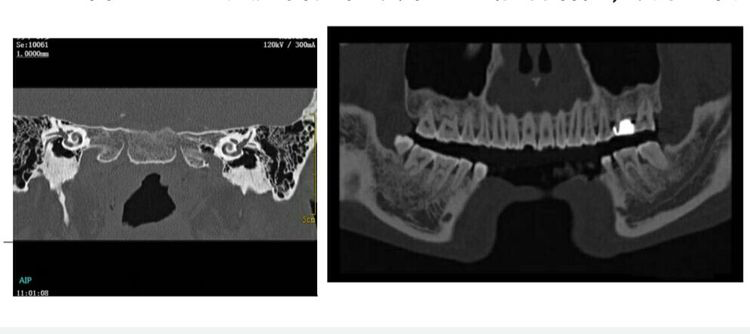

颅骨骨折(三维重建VR、MIP像) 下颌骨骨折

四.五官:

1024 大矩阵成像技术对于精细结构,如内耳、眼部等小器官、小病变具有更高清晰度和准确性。